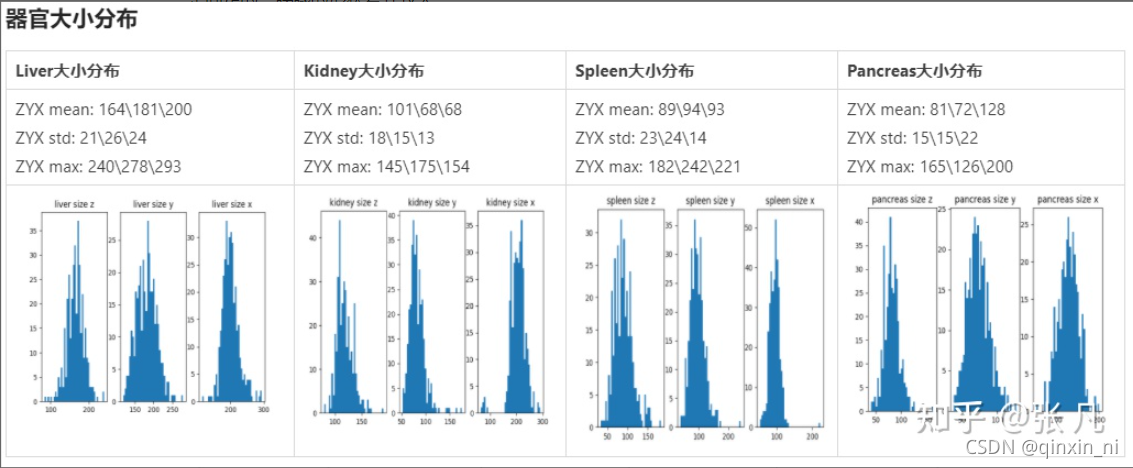

各个器官形状特征的分布如下。参考器官volume特征,设置保留最大连通区域的阈值;参考intensity特征,设置对比度增强参数;参考centroid_shift特征,统计器官之间的相对位置关系;参考axis_ratio特征,统计器官的形状差异。不同器官的大小符合正态分布;不同器官的相对位置是固定的;胰腺的形状差异较大。